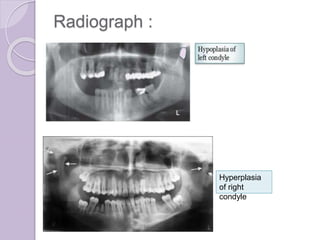

Condylar hyperplasia &

hypoplasia

Condylar hyperplasia

๏‚— Introduction

๏‚— Etiology : overactive cartilage

Clinical feature :

Condylar hypoplasia

๏‚— Etiology:

congenital โ€“ a/w syndrome

acquired โ€“ condyle injured during active

growth

Clinical features

Radiograph :

Hyperplasia

of right

condyle

๏‚— Treatment : orthodontics combined with

orthognathic surgey